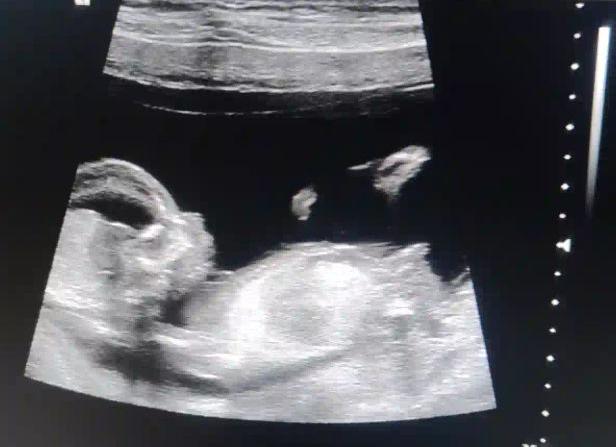

На первом скрининге можно узнать пол ребенка

Узнайте пол будущего ребенка, пройдя быструю и качественную УЗИ диагностику у специалистов нашего центра. При записи к нам по телефонам или заявке на сайте Вы получите скидку.

Каждая беременная женщина с начала беременности начинает гадать о том, кто же у нее родится: мальчик или девочка. В ход идут вычисления по календарю, изучение родословной мужа, различные приметы. Но одним из безопасных и более достоверных методов является ультразвуковая диагностика, проще говоря, УЗИ скрининг. УЗИ при беременности проводится три раза, иногда большее количество раз по назначению акушер-гинеколога. На 20 – 25 неделе проводится, как правило, второе УЗИ скрининг, на котором при благоприятных обстоятельствах будет виден пол ребенка. Но полностью доверять словам врача, проводящего УЗИ скрининг, не стоит, так он может ошибиться. Определить пол ребенка с точность 100% невозможно до его рождения. Нередко за половой орган мальчик малоопытный врач может принять часть пуповины. Ребенок может принять позу, неудобную для исследования его половых органов: повернуться попой к датчику УЗИ, закрыть ручками промежность и так далее. Подробнее ...